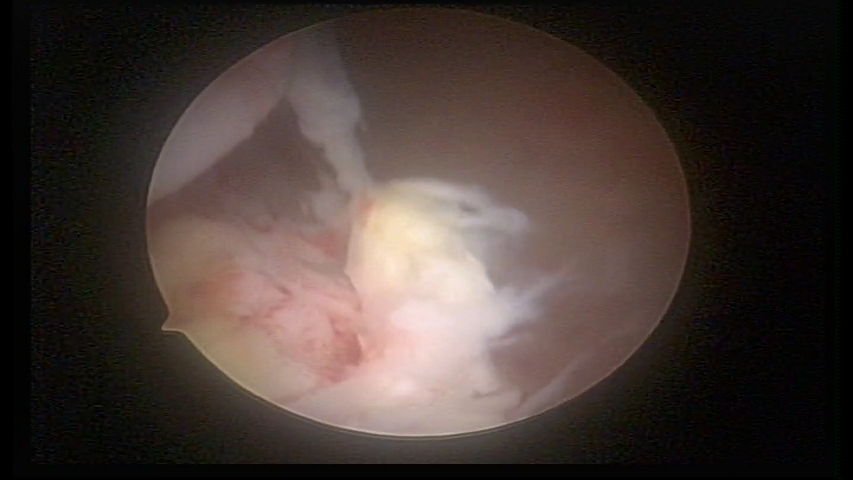

Retained trophoblastic material

trophoblastic material